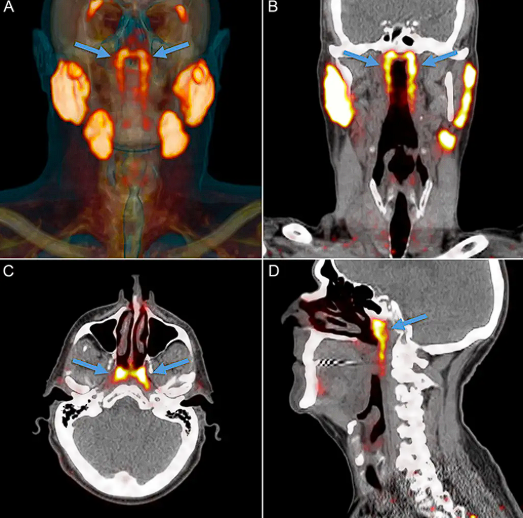

A novidade surgiu durante exames de PSMA PET/CT, um tipo de tomografia muito usado para detectar câncer de próstata. Enquanto avaliavam as imagens, os médicos se depararam com duas áreas simétricas e brilhantes, indicando intensa atividade glandular em uma região onde, até então, acreditava-se que só existiam glândulas microscópicas.

Para ter certeza de que não se tratava de algo raro, os cientistas analisaram 100 pacientes e, em todos eles, as glândulas apareceram. Isso confirma que se trata de uma característica comum da anatomia humana que passou despercebida até hoje.

As estruturas foram chamadas de “glândulas tubárias”, já que ficam próximas à tuba auditiva. Os pesquisadores acreditam que elas ajudam a umidificar a parte de trás da garganta, facilitando funções básicas como falar e engolir.